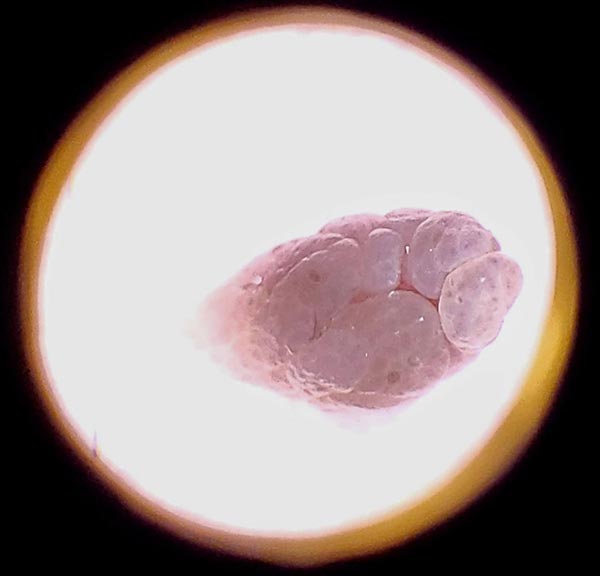

At Hideaway Spa, every growth is examined using a dermatoscope (dermlite) before treatment. This specialized magnification tool allows detailed visualization of skin structures to:

• Confirm the growth is indeed a benign skin tag (acrochordon)

• Rule out concerning features that require medical referral

• Assess blood supply and depth for appropriate treatment planning

• Document baseline appearance for clinical records

Any lesion exhibiting irregular features, suspicious pigmentation, or clinical uncertainty is referred to a physician or dermatologist before treatment proceeds.

skintag seen through a profressional dermlite at Hideaway Spa